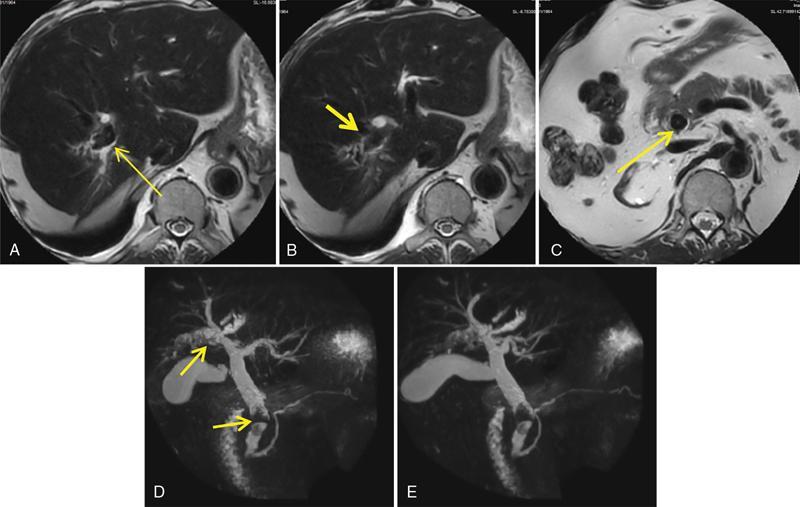

Ritu K. Kashikar, Shrinivas B. Desai, Chandresh Karnavat, Nilesh Doctor The biliary tract is subject to a variety of abnormalities. The spectrum includes benign diseases of autoimmune, infective, ischaemic, infiltrative aetiologies and malignant disorder, which most importantly represents cholangiocarcinoma. Imaging in particular magnetic resonance cholangiopancreatography (MRCP) plays a vital role in diagnosis and follow-up of these disorders. Multidetector computed tomography (MDCT) and magnetic resonance imaging (MRI) are also crucial in preoperative staging of biliary malignancies and making decisions regarding resectability and extent of resection. This chapter focuses on important benign and malignant disorders of the biliary tree and imaging features that aid in differentiation of various entities. A variety of disorders affect the biliary tree. Most biliary disorders manifest as biliary dilatation. The various causes are listed in Table 9.15.1. Imaging plays an important role in identification of aetiology based on pattern of involvement in association with clinical picture. USG is often the first investigation in a patient with jaundice. USG is excellent at showing biliary dilatation. It may be useless in assessing level of obstruction and biliary stones. Changes in liver morphology, development of cirrhosis is accurately done on USG. Early changes in conditions like primary sclerosing cholangitis (PSC), presence of intrahepatic ductal strictures, thickening of common bile duct (CBD) are, however, not confidently seen and need imaging modalities like MRCP and computed tomography (CT). Staging of hilar cancers is also best done on CT or MRI with contrast. Contrast-enhanced CT is extremely accurate in staging hilar cancers. It is a preferred modality to access radial spread of the disease and vascular involvement. Subtle changes of PSC and autoimmune cholangitis may however be missed and MRCP is preferred in these conditions. The protocol for evaluating biliary disease is standard plain scan followed by early, late arterial, portal venous and parenchymal phases similar to that obtained for focal liver lesions. Delayed phase images should be obtained for hilar malignancies, which often show delayed enhancement. MRCP with or without contrast is the modality of choice in diagnosing and characterizing biliary diseases. Owing to its noninvasive nature, it has replaced endoscopic retrograde cholangiopancreatography (ERCP) in the initial evaluation and follow-up of a variety of biliary pathologies. Absence of radiation exposure makes it suitable to obtain follow-ups in patients requiring serial scanning. The ability to diagnose abnormalities of both intra- and extrahepatic biliary tree, level of obstruction, longitudinal and radial spread of neoplastic process make it an ideal modality. MRCP protocol includes T2 weighted single-shot fast spin-echo, T1 weighted in phase and opposed phase gradient echo, diffusion-weighted imaging, T2-weighted fat-suppressed fast spin-echo in axial and coronal. A pre contrast three-dimensional T1-weighted fat-suppressed spoiled gradient-echo image is obtained in addition to 3-D MRCP. Postcontrast protocol includes dynamic three-dimensional T1-weighted fat-suppressed spoiled gradient-echo (in arterial, late arterial and portal venous, parenchymal and delayed phases). Since the advent and widespread use of MRCP, the utility of ERCP in diagnosing biliary pathologies has significantly reduced. ERCP is primarily used when stenting or other procedures need to be performed in the same setting. Although an invasive procedure with postprocedural risk of pancreatitis ERCP allows excellent depiction of biliary changes in conditions like PSC, recurrent pyogenic cholangitis (RPC) and IgG4-related disorders. Endoscopic USG (EUS) is an excellent modality in diagnosing lower bile duct pathologies and also has the added advantage of obtaining a biopsy in the same setting. EUS is less invasive than ERCP and overall safer. PSC is a premalignant cholestatic liver disorder characterized by bile duct strictures secondary to bile duct inflammation and fibrosis. Cirrhosis of liver can develop secondary to this condition and patients are at a high risk for biliary and colonic cancers. PSC is a relatively rare disease, with an incidence of less than 50 per 100,000 patients though it varies in various location. It is diagnosed in young patients aged 30–40 years and is twice as common in men than in women. Similar to other autoimmune diseases, genetic susceptibility is likely to be instrumental in the development of PSC after exposure to a trigger. There is also a strong association between PSC and human leukocyte antigens (HLAs). Environmental factors such as childhood microbial exposure also play an important role in disease pathogenesis. A strong association of PSC with inflammatory bowel disease (IBD) is seen. There is a 100-fold increased risk of developing PSC among siblings. PSC can be asymptomatic but may present with cholestatic symptoms such as jaundice, pruritus, fatigue and right upper quadrant pain, steatorrhoea and episodes of acute bacterial cholangitis. There is marked elevation of alkaline phosphatase (ALP). A twofold to threefold increase in serum alanine and aspartate aminotransferase (AST) can be seen. Elevated bilirubin is usually seen in advanced disease, malignancy or those with choledocholithiasis. Various serum antibodies can also be elevated in PSC. These have been enlisted in Table 9.15.2. On liver biopsy, classic pathologic features of periductal concentric fibrosis or ‘onion skin’, around the affected ducts can be seen. This is however not a pathognomonic finding and is seen in less than 40% of biopsy specimens. Therefore, biopsy is not routinely used as a diagnostic tool for PSC and is reserved primarily for disease staging. MRI with MRCP best depicts the biliary changes in PSC and is the modality of choice. While CT and USG may show biliary dilatation and changes of cirrhosis in advanced cases, they fail to show early changes (Table 9.15.3). USG is an effective modality for the visualization of dilatation and diffuse wall thickening of the extrahepatic bile duct. Other feature seen on USG is bright echogenic portal triad. However, the role of USG in the diagnosis of early PSC is limited owing to suboptimal assessment of the intrahepatic biliary ducts. Features of advanced disease such as heterogeneous coarse echogenicity can be readily detected with USG. The major benefit of performing US is to guide liver biopsy. Also, liver stiffness as assessed by transient elastography correlated well with the degree of liver fibrosis in PSC patients. CT can demonstrate some findings suggestive of sclerosing cholangitis such as focal, discontinuous, often peripheral intrahepatic biliary duct dilatation and thickening with enhancement of the bile ducts owing to inflammation. CT is effective in helping exclude other causes that can result in biliary stasis and dilatation such as hepatic and pancreatic lesions. CT is also excellent in diagnosing tumours, which may sometimes have similar presentation. Concomitant changes of IBD, if present, can be seen. However, CT is limited in assessment of biliary strictures and visualization of disease involving small peripheral bile duct, especially in the early stages of the disease. CT shows changes of cirrhosis in liver and assessing changes of portal hypertension. MRCP is diagnostic imaging modality of choice in the workup of patients with suspected PSC, as recommended by both the AASLD and EASL guidelines. MRCP has high diagnostic sensitivity (86%) and specificity (94%) for the detection of PSC (Table 9.15.3). Multifocal short segmental strictures in the intra- or extrahepatic biliary tree with intervening normal or dilated duct leading to beaded appearance are seen in early disease. The location in strictures is usually at the biliary bifurcation and are disproportionate to upstream dilatation. Advanced cases show pruning of peripheral biliary radicals secondary to advancing fibrosis obliterating the smaller ducts. An obtuse angle between the central and peripheral ducts is suggestive of PSC. Diverticula and webs also can be seen, though not pathognomonic (Table 9.15.4) (Figs. 9.15.1–9.15.3). Strictures of the CBD of less than 1.5 mm and of left, right or common hepatic duct (CHD) of less than 1 mm are defined as dominant stricture. A dominant stricture is associated with worse prognosis in part due to development of cholangiocarcinoma. MRCP plays an important role in raising the suspicion and guiding treatment. A dominant stricture may be confused with hilar cholangiocarcinoma on imaging and it is often impossible to distinguish the two based on imaging alone (Table 9.15.4) (Fig. 9.15.4). Changes in liver morphology are seen in the form of distortion. The classical change described in PSC includes hypertrophy of the caudate lobe and atrophy of the left lateral and right posterior segments of the liver. Hypertrophy of caudate lobe is more frequent in PSC than cirrhosis from other aetiologies. Other parenchymal changes include heterogeneity of liver, periportal cuffing, peripheral inflammation, cirrhosis and features of portal hypertension. Hyperintensity of the liver parenchyma in PSC on nonenhanced T1-weighted images has been reported. Wedge-shaped peripheral atrophic areas of confluent hepatic fibrosis are seen as high T2-weighted signal intensity. Periportal oedema is visualized as high signal intensity in periportal region on T2-weighted. Increased heterogeneous peripheral enhancement of the liver parenchyma can be seen and is likely due to the altered blood supply in those areas in response to parenchymal inflammation (Table 9.15.4) (Figs. 9.15.5 and 9.15.6). MR elastography is the most accurate noninvasive method for the diagnosis and staging of liver fibrosis and could potentially replace liver biopsy. It is predictive of progression to decompensated liver disease. However, lack of wide availability are still major limiting factors. MR elastography is not influenced by obesity or anatomical conditions (e.g. narrow intercostal spaces and ascites) and the sample size of the liver is significantly higher and hence has several advantages over ultrasound elastography (Table 9.15.5). Besides these features, enlarged reactive abdominal lymph nodes, commonly periportal and portocaval lymph nodes, are commonly diagnosed in PSC and should not be misdiagnosed as a lymphoproliferative disorder or metastatic disease. Though ERCP has higher diagnostic accuracy in detecting PSC, its role is limited to intervention required in PSC due to its invasive nature and potential complications. Also it is recommended that MRCP be performed prior to ERCP as a preprocedural MRCP can provide a road map to the endoscopist. Small duct PSC is a variant PSC syndrome with biochemical markers and histologic features suggestive of PSC with normal cholangiography. It is associated with better prognosis. Approximately one-fourth of patients’ progress to classic PSC in an average of 8 years. Bile duct calculi are a common complication of PSC. Pigmented bile duct stones are common owing to biliary stasis. Both intrahepatic and extrahepatic biliary stones can be found. However, the presence of biliary tree stones is not an essential diagnostic feature. Soft calcific foci within dilated bile ducts can be seen on US and CT images. MRI with MRCP is the imaging modality of choice to detect bile duct stones and appear as focal areas of signal-intensity-void filling defects on T2-weighted images. Usually isointense at T1-weighted imaging but frequently are hyperintense. The presence of biliary strictures puts these patients at risk of bacterial cholangitis in PSC patients. The classic Charcot triad of fever, abdominal pain and jaundice can be seen. Early enhancement of the biliary wall due to the biliary duct inflammation is a common finding with peribiliary reactive hepatic parenchymal changes. Cholangitic abscesses may sometimes be seen. PSC patients are at high risk of developing cholangiocarcinoma during the disease course with and a total risk of 10%–15%. Approximately 30% of all cholangiocarcinomas are detected within the first year of establishing a diagnosis of PSC and so it is important to be suspicious even at the time of PSC diagnosis and to survey for early detection. Rapid clinical deterioration, worsening of jaundice, pruritus, weight loss along with elevation in serum bilirubin and ALP should raise suspicion of PSC. It may be difficult to distinguish benign from malignant strictures. Progressive bile duct wall thickening, irregularity, enhancement, new onset biliary dilatation, dominant stricture or development of focal strictures with dilatation and ipsilateral atrophy are indeterminate features that may raise possibility if occult cholangiocarcinomas. Perivascular thickening, vascular involvement or occlusion are features favouring malignancy. Definite diagnosis is however often not possible on imaging alone and a brush biopsy should be taken in patients with new onset clinical symptoms, elevated tumour makers or above-mentioned indeterminate imaging features (Table 9.15.7). The most common subtype of cholangiocarcinoma in PSC patients is periductal type, characterized by long segment irregular wall thickening along the bile duct with no identifiable mass. The lesion is hypointense on T1W1 images and hyperintense on T2W1 images showing progressive enhancement on contrast study. The tumour could be at the bifurcation and can cause abrupt cut-off, commonly presenting as Klatskin tumour (Fig. 9.15.7). Combined UC and PSC is associated with a higher risk for colorectal carcinoma than UC alone. PSC is considered as an independent risk factor for development of colorectal carcinoma in patients with UC. Malignancy tends to involve the right colon or more proximal parts of the colon. Clinical presentation and history in patients with ascending cholangitis differ from those with PSC. Fever, pain and jaundice dominate the presentation in patients with ascending cholangitis while patients with PSC may be asymptomatic. The typical findings of PSC including biliary duct stenosis, beading or pruning are not typical findings in the newly diagnosed cases of acute ascending cholangitis. Wedge-shaped peripheral and/or intrahepatic peribiliary foci of increased T2 signal around the dilated radicals with arterial and/or delayed parenchymal enhancement has been described in ascending cholangitis. Patients with RPC present with recurrent episodes of abdominal pain, fever, jaundice and chills. These features differ from those in patients with PSC. Hepatolithiasis with pigmented stones in the biliary tree and upstream and downstream duct dilatation are typical imaging features in RPC (Table 9.15.8). Ischaemic cholangiopathy is a form of biliary injury resulting from decreased arterial supply. History of liver transplantation is the key in diagnosing ischaemic cholangiopathy. Biliary strictures in AIDS cholangiopathy are indistinguishable from PSC. However, the combination of papillary stenosis and intrahepatic ductal strictures appears relatively unique to AIDS cholangiopathy; this combination is not found in PSC. Clinical history may help to distinguish one from the other. Effective medical therapy for PSC is lacking. Oral ursodiol (ursodeoxycholic acid) is one of the main treatment options of cholestatic diseases though does not prevent disease progression. Azathioprine and steroids are recommended for use in patients with AIH as well as those with AIH–PSC overlap syndrome. Vedolizumab is a gut-specific monoclonal antibody that has been tried but the clinical utility in PSC–IBD patients remains under investigation. Dilatation of biliary strictures, stenting, lithotripsy and stone extraction can be done with the aid of ERCP and percutaneous transhepatic cholangiography (PTC). The only definitive cure of PSC is, however, liver transplantation. Treatment of complications like choledocholithiasis stone removal can be accomplished by using standard endoscopic techniques with or without sphincterotomy, with balloon or basket extraction for extrahepatic biliary stones. For bacterial cholangitis, immediate administration of broad-spectrum antibiotic therapy is recommended and in abscess formation percutaneous drainage with intravenous antibiotic therapy shows favourable outcome compared with surgical drainage. Incidence is 20%–25%. Diagnosis of recurrent PSC requires careful evaluation, as there are other causes of biliary changes after liver transplant with similar features. Nonanastomotic biliary strictures imply the diagnosis of recurrent PSC only if they occur more than 90 days after transplant. Characteristic multifocal strictures and segmental dilatations of biliary ducts are suggestive findings. MRCP is the initial modality. RPC is characterized by a triad of recurrent biliary sepsis, inflammatory biliary strictures and intrahepatic stones. Fifty per cent of patients may have acute pancreatitis. Oriental cholangiohepatitis, primary hepatolithiasis, Hong Kong disease and oriental infestational cholangitis. Prevalence in the third and fourth decades of life with equal frequency among men and women peak. Southeast Asia predominantly in rural population and in lower socioeconomic groups. Gut-derived organisms lead to sepsis, which initiates a cascade of events, which leads to a chronic, progressive and recurrent inflammatory process in cholangioles. Associations with Clonorchis sinensis, Opisthorchis species, Fasciola hepatica and Ascaris lumbricoides infestations have been suggested. Common organisms cultured from bile include Escherichia coli, Klebsiella, Pseudomonas and Proteus species and anaerobes. Structural biliary abnormalities may develop before stones are demonstrable. Strictures may be seen at cholangiography without stones and vice versa. Entrapped stones cause stasis, sepsis, scarring and stricturing with the increasing lithogenicity (Table 9.15.9). Typically present with abdominal pain, fever and jaundice (the Charcot triad) and commonly provide history of repeated episodes. Routine investigations may demonstrate leukocytosis, deranged liver enzymes with obstructive pattern. Elevated cholestatic markers (bilirubin, ALP and gamma GT) and deranged LFTs can be seen. Serum inflammatory markers can be elevated. Additional tests aiding in differential diagnosis include autoantibodies, ANCA, CA19-9 and serologic tests for Echinococcus. Histology is usually not required. It shows fibrous mural thickening of bile ducts and periductal tissue, as well as acute and chronic inflammatory changes. The imaging features include changes in bile ducts, development of calculi and changes in the parenchyma. The disease affects intrahepatic ducts more than the CHD and CBD. Disproportional dilatation of central intrahepatic ducts and extrahepatic bile ducts is seen with nondilated or minimally dilated peripheral ducts, leading to abrupt tapering of bile ducts. All segments of biliary tree may be involved, but the lateral segment of the left lobe is most often and extensively involved most likely because left hepatic ducts come off at a more acute angle compared with the right hepatic ducts, thus predisposing to stasis and stricture formation (Table 9.15.10). Hepatolithiasis is common in patients with RPC. Stones are composed mainly of bile pigments with variable calcification. There may be single or multiple stones scattered in the intra- or extrahepatic ducts or both. The dilatation of the extrahepatic duct is generally not related to the location of the stone. Ducts both proximal and distal to the stone are dilated. Parenchymal atrophy most commonly involves the left lateral and right posterior segments while hypertrophy of the caudate and right lobe is seen. USG shows dilatation of the central intrahepatic and extrahepatic ducts, with relative sparing of the peripheral biliary tree. Hepatolithiasis can be seen in 90% of cases. The echogenicity and acoustic shadowing of calculi may vary depending on extent of calcification. There is often associated periportal echogenicity. Ultrasound may be useful in performing image-guided percutaneous drainage of abscesses or biopsy of suspicious lesions. Limitations include inability to detect subtle intrahepatic ductal dilatation and heavy stone burden obscuring evaluation of underlying hepatic parenchyma. Contrast-enhanced CT is increasingly being used as first line of imaging. It allows for detection of characteristic disproportionate dilatation of the extrahepatic and central intrahepatic ducts. Contrast-enhanced CT also allows for detection of bile duct wall enhancement, suggestive of acute cholangitis. Ninety per cent stones are hyperdense to liver parenchyma on nonenhanced scan. Extent of calcification in calculi may vary. Parenchymal atrophy affects left lateral segment most frequently, followed by right posterior segments. Eventually, changes of cirrhosis can be seen. Heterogeneous appearance of liver parenchyma with segmental steatosis and altered enhancement can be seen particularly during acute attack. Pneumobilia is not infrequent and can usually be attributed to recent procedures or surgeries like bilioenteric anastomosis. It may, however, be seen in patients without history of prior interventions due to recent passage of stone through the ampulla or less commonly cholangitis related to gas forming organisms (Fig. 9.15.8). Subtle intrahepatic ductal strictures and noncalcified stones may be missed on CT. MRCP allows visualization of both intra- and extraductal disease and can reveal complete extent, severity and complications of the disease. Even noncalcified calculi which may be missed on CT or sonography, are seen as intraductal filling defects on heavily T2-weighted images and may appear hyperintense to the liver on T1-weighted images. MRI demonstrates central and extrahepatic duct dilatation with decreased arborization and abrupt tapering of peripheral ducts. MRI particularly MRCP sequences accurately depicts stenotic segments and delineates the entire biliary tree, including the proximal part of the stricture, without risk of aggravating biliary sepsis. Even short segment duct strictures <1 cm are easily seen on MRCP (Figs. 9.15.8 and 9.15.9). Parenchymal abnormalities like hepatic atrophy, whether diffuse or segmental, and altered signal can be accurately diagnosed. Mass lesions and hepatic abscesses, if present, are also well delineated. The characteristic finding of disproportionate dilatation of the ducts, with multiple intraductal calculi are well demonstrated. There may also be intrahepatic strictures, with abrupt tapering of the peripheral ducts as well as decreased arborization of the biliary tree (arrowhead appearance). It allows for better spatial resolution, thus permitting better evaluation of the smaller peripheral ducts. The main limitation of ERCP is its invasive nature, with complications such as ERCP-associated pancreatitis. Heterogeneous parenchymal enhancement, wall thickening and periductal enhancement are seen in acute cholangitis. Abscess formation is encountered in up to 20% of RPC patients who undergo cross-sectional imaging. The abscesses can occur in both the affected and unaffected portions of the liver but most commonly seen in the right lobe. Sonography guided aspiration can be done when diagnosis is doubtful. Intrahepatic bile lakes are not infrequent and may or may not communicate with the biliary tree. On USG bilomas appear anechoic and are usually hypodense on CT with or without calculi. Leakage of bile from a severely dilated obstructed duct may lead to formation of extrahepatic biloma. Cholangiocarcinoma is the most feared complication and may be seen in up to 5% of patients. Segments with high stone burden or those with atrophy are more prone to developing cholangiocarcinoma. Clinical and laboratory indicators for development of cholangiocarcinoma in patients with PSC include increase in jaundice without associated cholangitis, sudden weight loss, significant elevation of ALP and rising tumour markers. Peripheral cholangiocarcinoma manifests as expansion of the affected segment. Hypoattenuating mass with showing peripheral enhancement causing narrowing of the portal vein may raise suspicion of malignancy. Portal vein thrombosis has also been reported but is rare. Recurrent biliary sepsis may lead to periductal inflammation and portal thrombophlebitis. Portal thrombosis can lead to lobar atrophy with compensatory hypertrophy of the uninvolved lobe. Higher incidence of hepatocellular carcinoma (HCC) is reported in patients with RPC due to development of cirrhosis in severe cases. Management should comprise antibiotic treatment, clearance of stones, maintenance of biliary drainage and long-term follow-ups. ERCP allows for therapeutic procedures such as stone removal and stenting of strictures. Destroyed liver segments, those with multiple abscesses and patients with secondary cholangiocarcinoma are candidates or surgery. Stone extraction can also be done surgically with the aid of basket, forceps, balloon catheter or flexible choledochoscope. Transduodenal sphincteroplasty and hepaticojejunostomy are commonly performed drainage procedures. Indications for transplantation include extensive bilobar hepatolithiasis, cirrhosis and liver failure. IgG4 cholangiopathy is a cholangitis characterized by elevated serum IgG4 and infiltration of the bile duct wall with IgG4 positive plasma cells leading to storiform fibrosis and obliterative phlebitis with resultant bile duct wall thickening. This condition shows good response to steroids. Frequent association with IgG4-related autoimmune pancreatitis is seen. IgG4 sclerosing cholangitis (IgG4-SC) has a threefold to fivefold higher prevalence in men than women. It usually presents in the fifth and sixth decades of life. Incidence of this disease is approximated to be around 0.28–1.08/100,000. Autoimmunity has been considered as the most probable pathogenesis of IgG4-related disease (IgG4-RD). Several HLA association have identified as determinants of disease susceptibility. The major histologic features associated with IgG4-RD have been well described and include the steps. Chronic or recurrent cholangitis is the most common presentation and seen in up to 75% cases. Other symptoms seen are fever, pruritus, pain and weight loss. Biliary involvement may be detected incidentally in patients being scanned for symptoms related to involvement of other organs such as pancreas. One-quarter of patients with IgG4-SC may be asymptomatic. Serum liver tests show a cholestatic pattern with often marked elevation of ALP and γ-GT and only mildly increased ALT and AST. Serum bilirubin may be increased. Tumour marker CA 19-9 is not able to distinguish pancreatobiliary malignancies from IgG4-SC since levels of >1000 IU/mL (ULN = 37 IU/mL) may be observed in IgG4-SC. IgG4 levels are elevated (>140 mg/dL) in up to 75%–80% of affected patients. A cut-off level of 207 mg/dL might be useful for completely distinguishing IgG4-SC from cholangiocarcinoma. Elevated bile fluid IgG4 has a high sensitivity and specificity of 100% at a cut-off level of 113 mg/dL and seen only in cases of IgG4-RD, neither PSC nor cholangiocarcinoma. Approximately 40% of patients have peripheral blood eosinophilia, often accompanied by asthma and atopy. Patients may show hypergammaglobulinemia, elevated serum IgE. Several diagnostic criteria have been developed to aid in the diagnosis of IgG4-SC. The most widely used is the HISORt (Histology, Imaging, Serology, other Organ involvement and Response to therapy) criteria of the Mayo Clinic. This tool was initially used to diagnose AIP but can be adapted to diagnose IgG4-SC by Ghazele et al. (Tables 9.15.13 and 9.15.14). It is often the initial investigation and may be normal early in the course of the disease. Circumferential thickening of the bile ducts with biliary dilatation is seen later in the disease. US also helps in the identification of associated findings affecting other organs. However, US has low sensitivity in detecting the disease and is suboptimal for assessing the extent of the disease. Contrast-enhanced CT though not the investigation of choice shows bile duct wall thickening with proximal mild dilatation. The intrapancreatic bile duct segment is more commonly involved. The most important finding is circumferential symmetric wall thickening of the bile ducts, frequently involving the extrahepatic segments, with smooth outer and inner margins. In addition, the thickened segment shows progressive homogeneous contrast enhancement, further increasing in the delayed phase. As opposed to malignancies, wall thickening or stricturing of bile ducts in IgG4-RD is not associated with proportionate proximal biliary dilatation (Figs. 9.15.10 and 9.15.11). In addition to the above findings, imaging findings of IgG4 disease affecting other organs, that is, gallbladder wall thickening, changes of autoimmune pancreatitis, retroperitoneal fibrosis and kidney findings can be seen. MRI is the investigation of choice. MRI findings are similar to CT findings and include circular and symmetric long segmental thickening of the bile duct wall with smooth outer and inner margins. Bile duct wall thickening can be seen in nonstenotic areas as well The other findings are the visibility of patent bile duct in the strictures, disproportionate proximal dilatation, hyperenhancement during the late arterial phase, homogeneous hyperenhancement during the delayed phase, concurrent gallbladder wall thickening and no vascular invasion (Table 9.15.15).